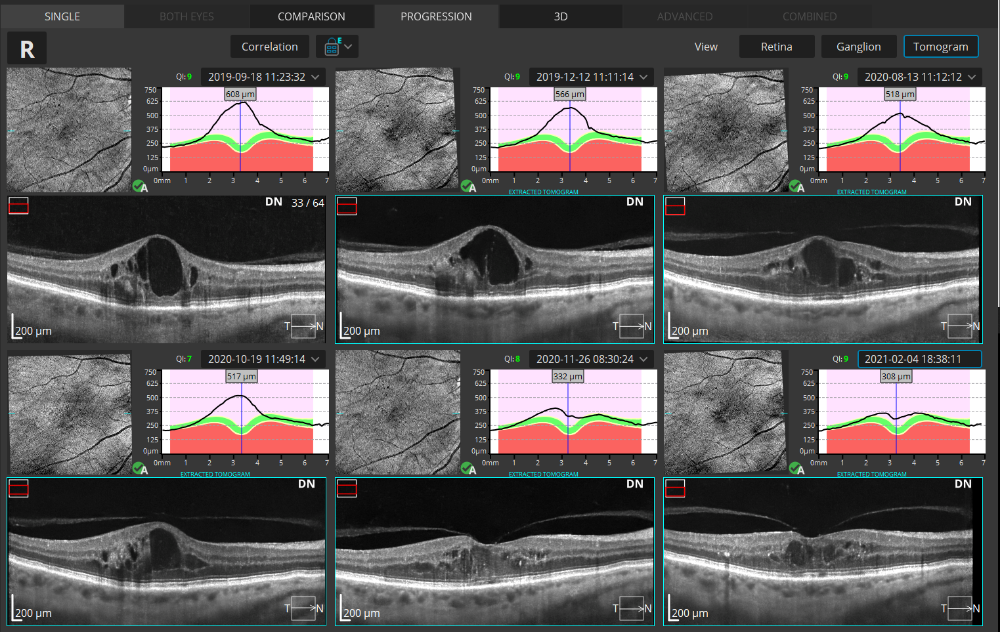

Retina B-scan Vue unique

Amélioration de la qualité des tomographies grâce à l'intelligence artificielle. Les algorithmes d'IA avancés améliorent la qualité d'un seul tomogramme au niveau d'un tomogramme moyen obtenu par plusieurs scans. L'algorithme AI DeNoise filtre le bruit du tomogramme pour une qualité d'image optimale et fluide. La fonction est disponible sur tous les tomogrammes et dans tous les onglets les présentant, y compris l'onglet 3D. Sur les tomographies moyennes, la fonction est activée par défaut. Au moment où un tomogramme est chargé pour examen, le logiciel commence à le débruiter. Après un court instant, le tomogramme original "sans bruit" est remplacé par une image sans bruit.